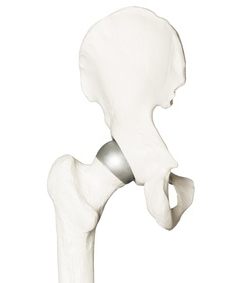

Aufbau und Funktion moderner Hüftprothesen

Das biologische Hüftgelenk besteht aus dem kugelförmigen Oberschenkelkopf und der ihm gegenüberliegenden Hüftpfanne (Acetabulum). Dazwischen sorgt Gelenkknorpel als Gleitschicht für eine Dämpfung des mechanischen Drucks durch die Gelenkbewegung und reduziert massiv die Reibung der Gelenkpartner.

Aufbau und Bestandteile einer Hüftprothese

Als künstliches Hüftgelenk wird üblicherweise eine Hüfttotalendoprothese, kurz Hüft-TEP, eingesetzt. Die vollständige Hüftprothese ersetzt beide knöchernen Teile des Hüftgelenks: den Hüftkopf (Femurkopf) und die Hüftpfanne (Acetabulum) und setzt sich aus folgenden Komponenten zusammen:

- im Oberschenkelknochen verankerter Prothesenschaft,

- runder Prothesenkopf,

- Inlay als Gleitkomponente,

- Implantat in der Hüftgelenkspfanne.

Der Arzt verankert die Hüftprothese fest im Oberschenkel- und im Beckenknochen des Patienten.